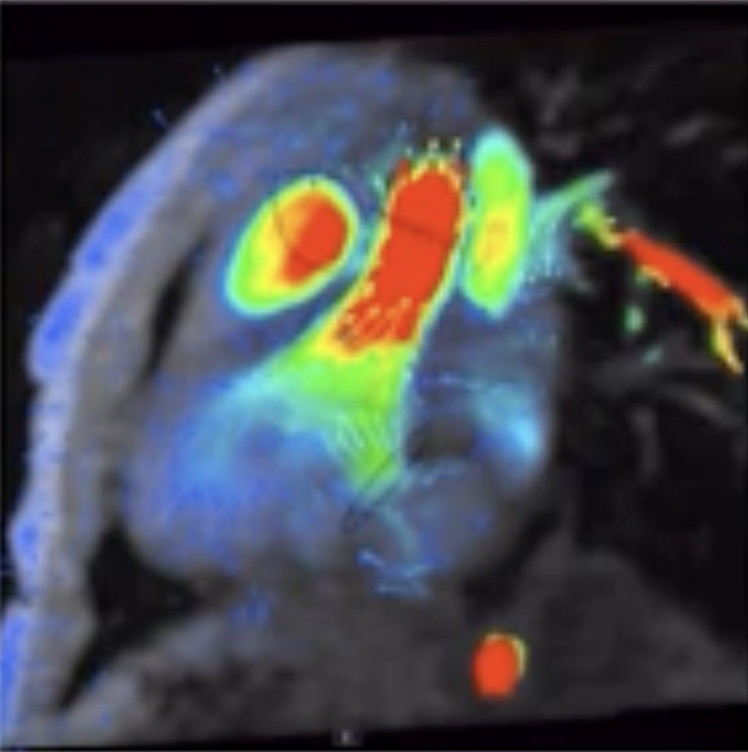

Det är en stor studie där barnen genomgår flera olika undersökningar under tre dagar. Det handlar bland annat om arbetsprov med gasanalys, hjärtultraljud, lungfunktionsundersökningar, MR av hjärta och lever, samt undersökningar av lymfsystem och blodkärl.

En annan viktig observation är att MR av hjärtat verkar ge den mest tillförlitliga bilden av hjärtfunktionen vid enkammarcirkulation. Forskarna har också sett att ökad stelhet i levern hänger ihop med förändringar i lungblodflödet.